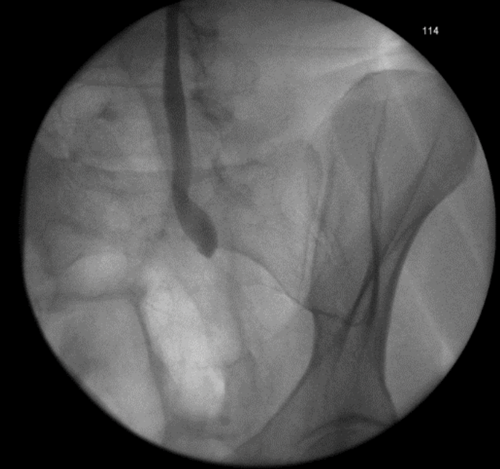

3a. Right antegrade wire insertion and pull-through.

3b. Right JJ stent in situ. Failed left antegrade wire passage.

3c. Left intraoperative nephrostogram showing obliterated left distal ureter.

3d. Right nephrostogram one week postoperative.

Figure 3: A 51-year-old woman, initially presenting with acute kidney injury, with bilateral distal ureteric obstruction secondary to locally advanced cervical cancer. Bilateral rendezvous, technically successful on right but failed on left secondary to ureterovaginal fistula.